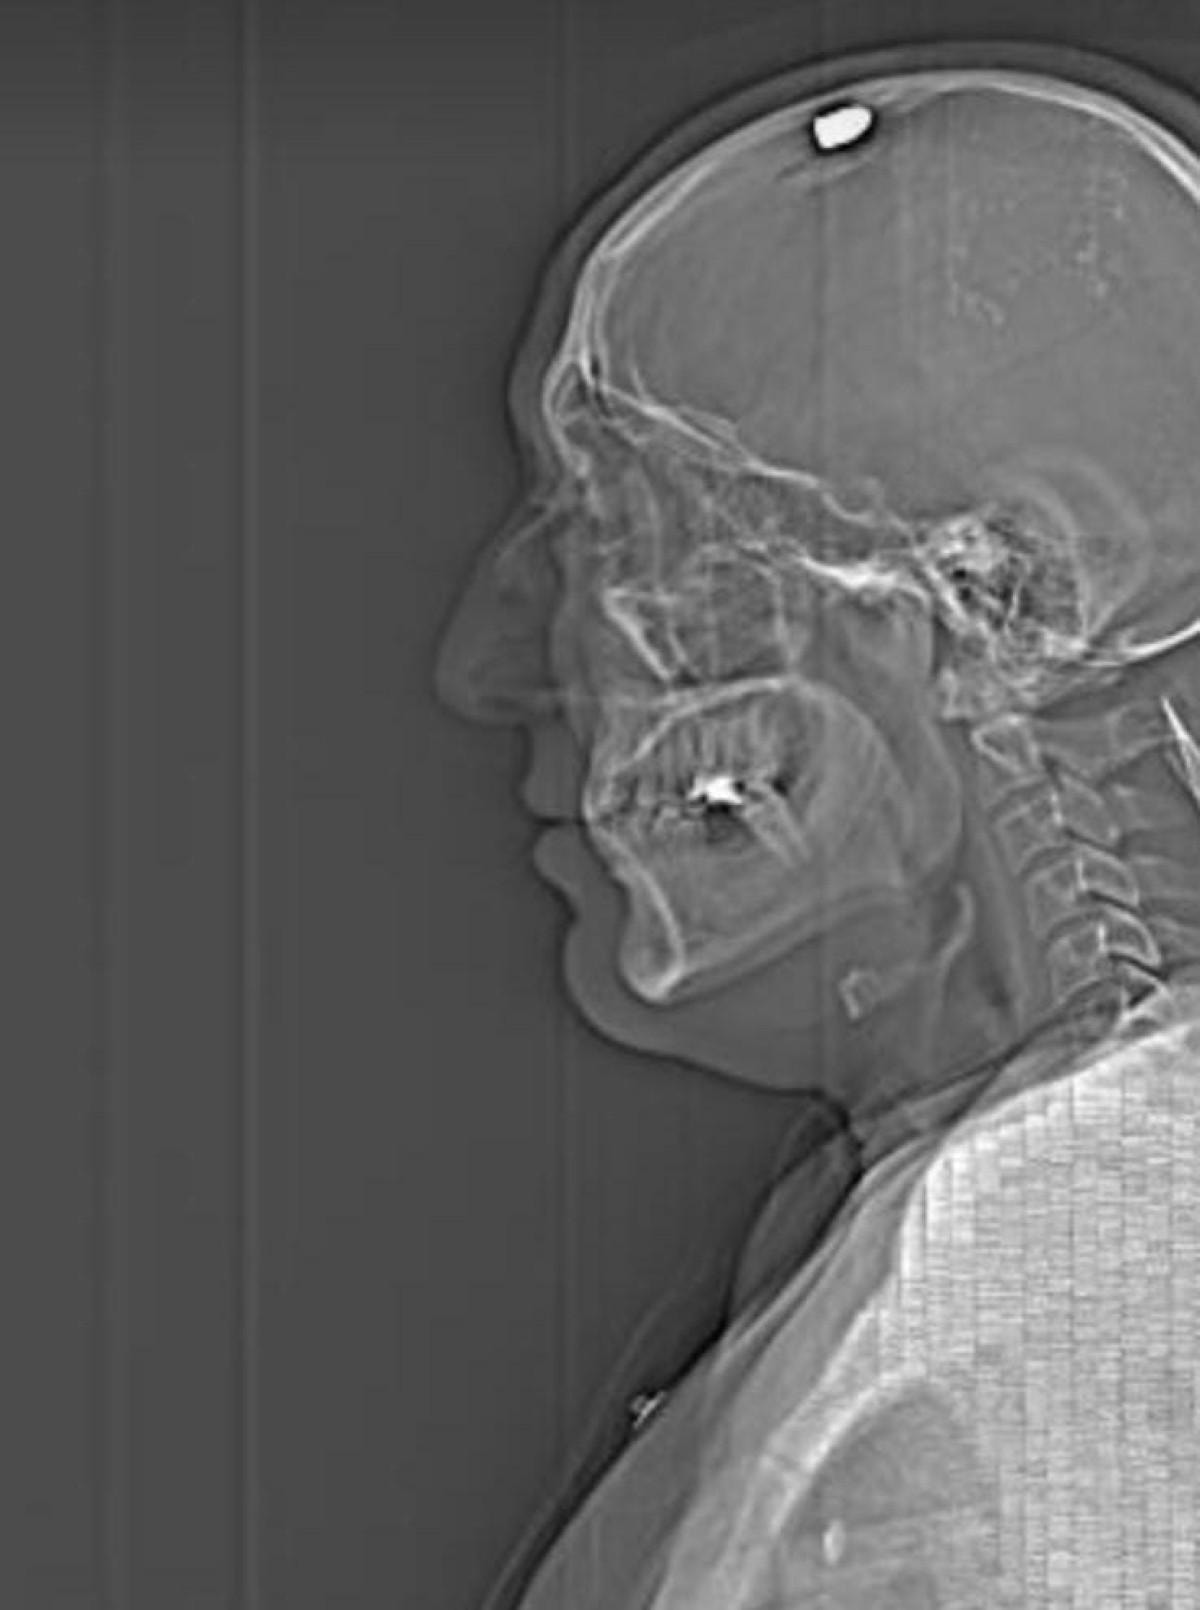

Savaş Koç'un avukatı Ali Erdem Gündoğan ise "Müvekkilin başına hedef alarak ateş ediyor. Kurşun beyine çok fazla zarar vermeden beyin tasının orada kalıyor. Müvekkil yere düşerken her şeyin farkında ve diyor ki 'Ben o anda olayların hepsini görüyordum; fakat tekrar bana ateş etmesinler' düşüncesiyle hareketsiz kalıyor, ölü taklidi yapıyor. Daha sonra bu şahıslar yakalanıyor. Müvekkil bunların kendilerini öldürme kastıyla geldiklerini söylüyor. Aslında müvekkil başkasının yerine kendini feda etmiştir. Yani o şahsın adresini vermiş olsaydı, o şahsı vuracaklardı. Adresi vermediği için müvekkili vuruyorlar" diye konuştu.